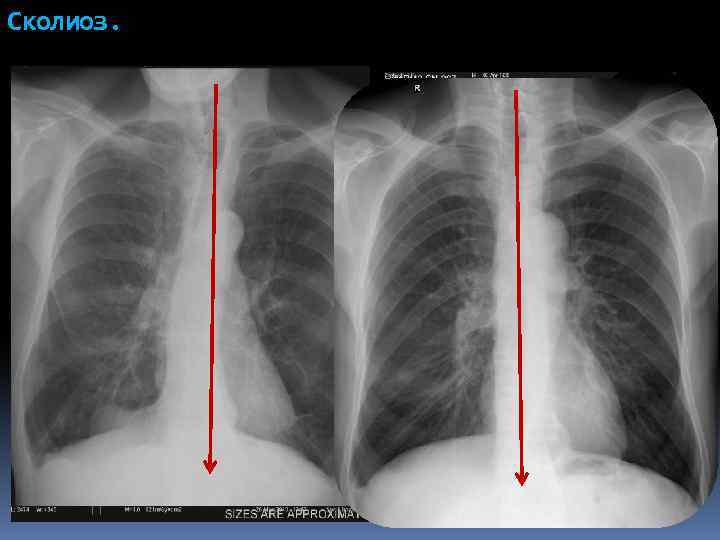

Сколиоз.